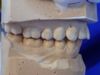

Mann kann hier sehr gut an den beiden Punkten der distalen Dreipunktabstützung erkennen, mit welch hoher Passgenauigkeit die Zentrikplatten auf die Gipszähne der Meistermodelle aufgebacht werden können und müssen.

Es ist einer dieser Detailpunkte, der darüber entscheidet, mit welcher Anfangspassgenauigkeit ein 'A'ufbissbehelf am Ende eines langwierigen Arbeitsprozesses in der Mundhöhle des Patienten eingeglidert werden kann.